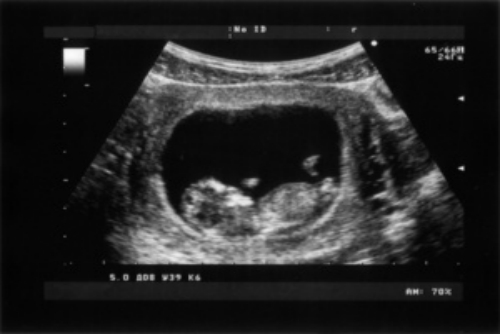

產前超聲檢查,一般包括胎兒的大小、胎位、羊水、胎盤等方面的檢查。通過產前超聲檢查,可以對胎兒的發育情況進行大體判斷,從而評估能否順利分娩。

1、胎兒的大小:通過超聲檢查測量胎兒的雙頂徑、頭圍、腹圍、股骨長等,評估胎兒體重。若胎兒體重過大,可能會增加分娩的難度,建議孕婦進行催產或剖宮產;

2、胎位:正常的胎位為頭位,即胎兒頭部朝下,臀部朝上,若胎兒的臀部朝下,可能是臀位,若胎兒頭部朝上,可能是橫位;

3、羊水:通過超聲檢查羊水深度、指數、羊水指數等,判斷羊水量是否正常,若羊水量偏少,可能會影響胎兒的發育,建議孕婦進行催產或剖宮產;

4、胎盤:通過超聲檢查了解胎盤的成熟度,判斷是否存在老化或鈣化。若胎盤鈣化或存在老化,可能會影響胎兒血液和營養物質的供應,進而影響胎兒的生長發育,建議孕婦進行催產或剖宮產;

5、臍帶:通過超聲檢查了解臍帶的長度、基部、彎曲度等情況,若有臍帶繞頸或臍帶扭轉的情況,需要進行急救,若臍帶過長或過細,可能會影響到胎兒的血液和營養供給,建議孕婦進行催產或剖宮產。

除上述項目外,產前超聲檢查還包括胎心監護、胎位檢查等。一般在孕晚期建議孕婦進行超聲檢查,因為通過超聲檢查能夠了解胎兒的生長發育情況,以及羊水、胎盤、臍帶等情況。若孕婦進行超聲檢查出現異常情況時,應及時到醫院就診。